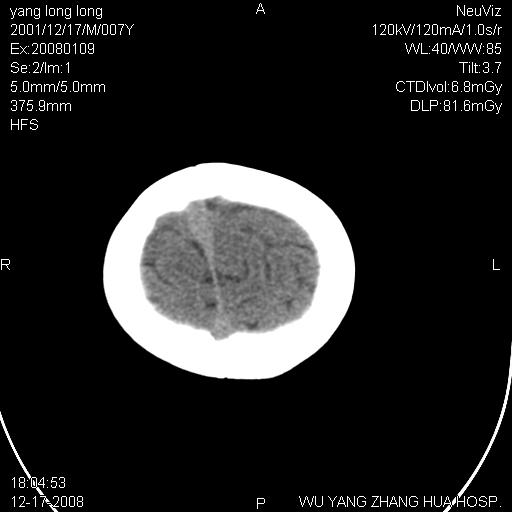

标题: PED1686:M7Y,头外伤,家人及自诉平时无任何不适。 [打印本页]

标题: PED1686:M7Y,头外伤,家人及自诉平时无任何不适。

考虑蛛网膜囊肿,请老师们看看多指导指导。

多考虑大枕大池。本例颅骨歪歪的,灶后枕骨似有膨胀征像(为蛛网膜囊肿征像),但整个左侧枕叶后方枕骨均有向后膨隆,所以暂不考虑蛛网膜囊肿。必要时随访